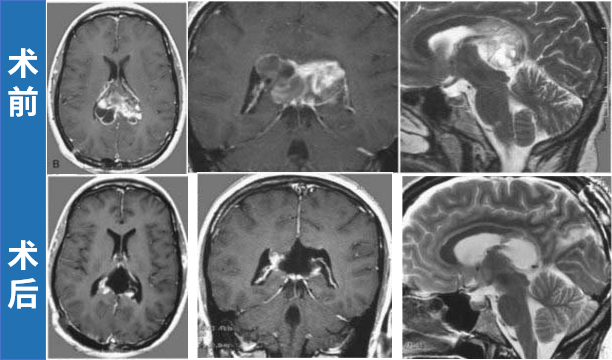

33岁孕妈妈Olive,孕期被严重头痛折磨,还出现走路不稳及轻度记忆减退,检查发现双侧侧脑室巨大肿瘤,还合并了脑积水的症状。考虑到患者情况立即进行囊液引流和肿瘤活检以释放颅内压,活检显示为毛细胞型星形细胞瘤,Olive迅速恢复,怀孕期间无需进一步治疗。

磁共振成像(MRI)在轴位(左上、左下)、冠状位(右上)和矢状位(右下)显示一个大型囊性肿瘤,占据双侧侧脑室后部。

但巨大的肿瘤仍是威胁,幸运的是,Olive顺利分娩。随后接受了择期手术,INC巴教授将肿瘤完全切除,同时保留了双侧胼胝体。术后,患者在数周内出现轻度记忆减退;此后,未出现任何神经或认知功能缺损,随访MRI显示肿瘤无复发。